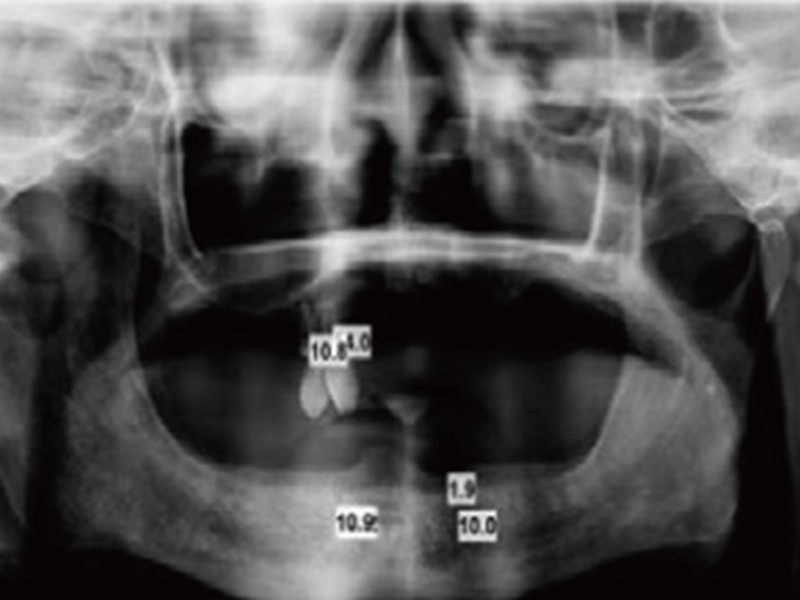

1. chụp X-quang

Chụp X-quang và quyết định vị trí đặt cho cấy ghép nha khoa.